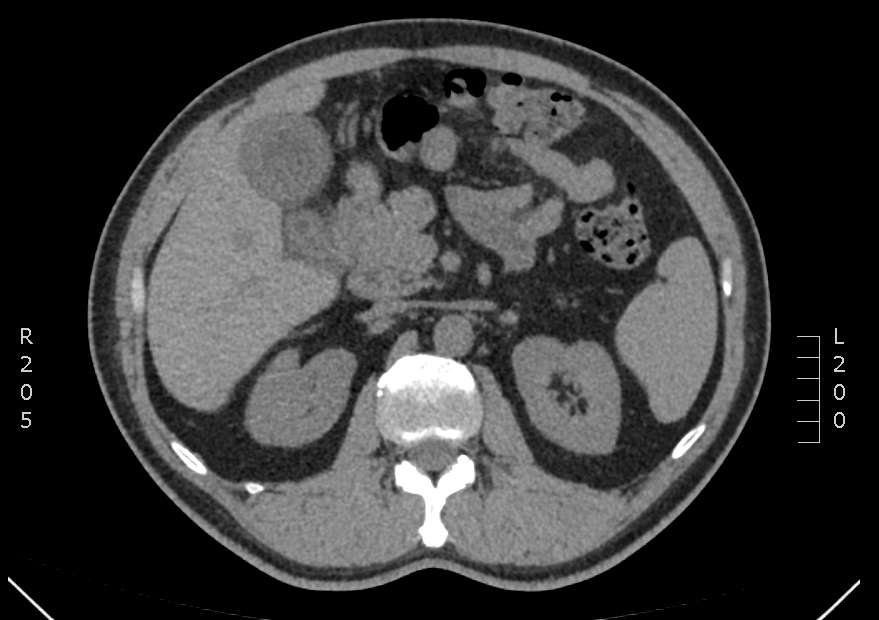

什么是胆总管结石?人的胆道系统非常复杂,而且与外貌类似,一人一个样子,大体上可以分为肝内胆管、肝总管、胆囊、胆总管。胆汁由肝脏产生,经各级胆管汇合,流入胆总管。当未在进食时,胆总管末端的括约肌收缩,胆汁流入胆囊中暂存;进食后,括约肌开放,胆汁经十二指肠乳头进入肠道帮助消化。胆结石的形成原因复杂,至今尚未完全清楚,结石存在于胆道不同的位置会引起不同的症状。胆总管结石通常会导致急性炎症,出现腹痛、寒战、发热、黄疸(皮肤黏膜黄染、尿液发黄),严重者称为急性梗阻化脓性胆管炎(AOSC),可在数小时内危及生命;也可以导致慢性炎症,反复出现腹痛、黄疸、纳差、乏力,严重影响生活质量;结石长期存留还会导致胆管癌[1]。

那么,胆总管结石从何而来?大部分普通人和部分外科医生认为,胆总管结石大都是胆囊或肝内胆管形成结石后掉落下来的继发性结石,胆总管原发结石占比很小[2]。但该假设尚未得到严格的证实,而且胆道外科医生在治疗胆总管结石时也经常会发现一些难以解释的情况:有些成块的胆总管结石直径远大于胆囊管,它是如何从胆囊中掉落下来的?胆囊管的管径大多在2~3mm,而十二指肠乳头开口直径在2.6~3mm,如果结石能从胆囊中经胆囊管落入胆总管,那它为什么不能再经乳头进入肠道呢?胆囊切除术后的病人,一段时间后发现胆总管内出现了新的结石,这些结石又是从何而来呢?以上这些疑问实际上已经有了答案:胆总管结石的形成与胆道环境的改变有关,而胆道环境改变主要是因为胆道内液体流速和流向的变化[3]。在正常情况下,胆汁应通过十二指肠乳头单向流入肠道,胰腺分泌的胰液也应通过十二指肠乳头单向流入肠道,胆汁和胰液不应发生反流,肠液也不应反流入胆总管或胰管。

当出现先天发育异常、或后天发生胆胰管汇合部疾病时,就会出现胆胰管合流异常(PBM)或隐匿性胰胆管反流(OPBR),胰液或肠液就会反流进入胆总管,此情况会导致胰酶在胆总管中被激活,引起胆管黏膜组织、细胞、蛋白质、DNA及RNA的损伤,进而导致结石的形成[4-6]。